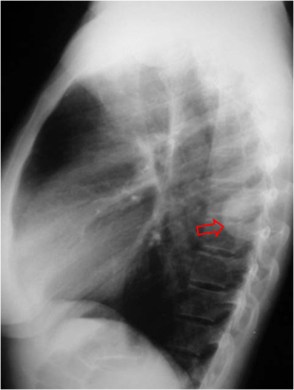

Signo de rotura diafragmática en TC, que consiste en la ausencia de un segmento del diafragma en uno o más cortes. La imágenes corresponden a un paciente con rotura traumática del hemidiafragma izquierdo. En la secuencia de cortes en la zona de transición toraco-abdominal no se ve el hemidiafragma izquierdo en ningún momento. Flecha roja: ángulo esplénico del colon herniado. Flecha blanca: estómago herniado con nivel hidroaéreo. Flecha verdenegra: bazo.